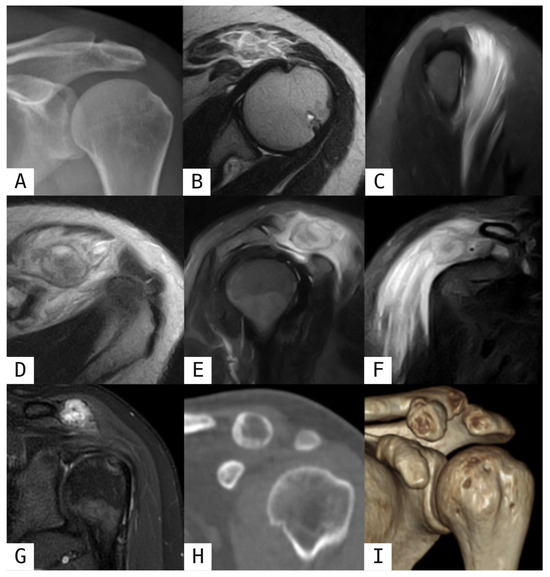

Revisiting Myositis Ossificans: A Comprehensive Stage-by-Stage Imaging Review

by Consolato Gullì, Giuseppe Ferrara, Emanuele Ferravante, Roberto Calbi, Mario Di Diego, Davide Parisi, Daniele Perla, Tommaso Villa and Luigi Natale

Muscles 2026, 5(2), 27; https://doi.org/10.3390/muscles5020027 - 14 Apr 2026

Myositis ossificans (MO) is a benign, self-limiting heterotopic ossification process that typically develops within soft tissues following trauma, although non-traumatic forms have also been described. Despite its benign nature, MO frequently represents a diagnostic challenge, particularly in its early stages when imaging findings [...] Read more.

Myositis ossificans (MO) is a benign, self-limiting heterotopic ossification process that typically develops within soft tissues following trauma, although non-traumatic forms have also been described. Despite its benign nature, MO frequently represents a diagnostic challenge, particularly in its early stages when imaging findings may mimic aggressive soft-tissue tumors, leading to unnecessary biopsies or surgical interventions. This narrative review provides an updated overview of the classification, pathophysiology, and imaging features of myositis ossificans, with a specific focus on the time-dependent evolution of radiologic appearances across different imaging modalities. Radiologic findings are discussed according to disease stage, highlighting key diagnostic clues such as the zonal phenomenon and peripheral maturation pattern. In addition, the main entities included in the differential diagnosis are reviewed, with particular emphasis on imaging features that help distinguish myositis ossificans from soft-tissue sarcomas and other calcified or ossified lesions. Finally, current management strategies and the role of imaging in patient follow-up are summarized. A thorough understanding of the evolving imaging spectrum of myositis ossificans is essential for radiologists and clinicians to achieve an accurate diagnosis, guide appropriate management, and avoid overtreatment. Full article

Show Figures

Figure 1